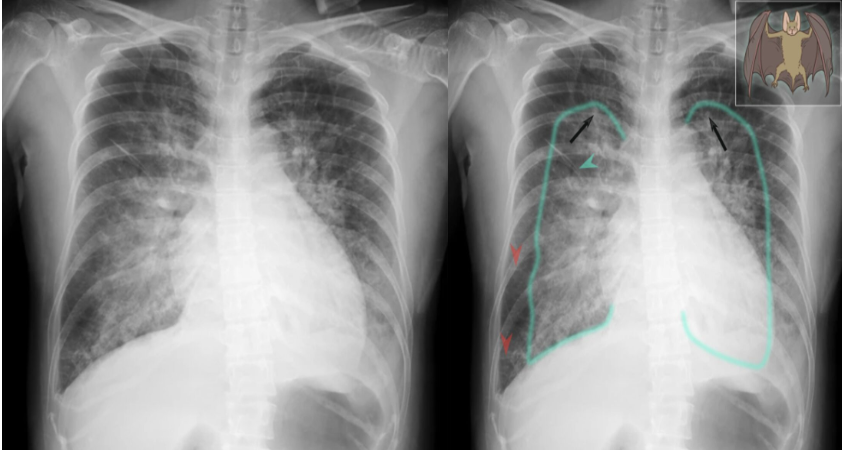

X-ray chest (PA view)

of a patient in the 3rd trimester of pregnancy with peripartum cardiomyopathy

The cardiac silhouette is enlarged and upper lobe vessels are prominent (redistribution of flow). Bilateral interstitial and airspace edema is predominantly perihilar in distribution and produces a classic batwing, or butterfly, appearance. Pulmonary vessel margins are obscured (perihilar haze) and thickened interlobular septae (Kerley lines) are conspicuous.